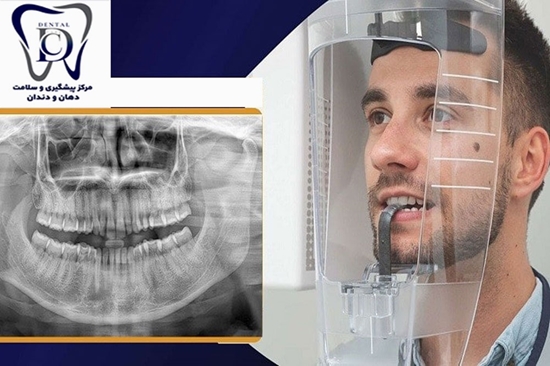

هفدهم آبان‌ماه در تقویم سلامت کشور، به عنوان «روز رادیولوژی دندانپزشکی» نام‌گذاری شده است. این مناسبت، فرصتی است برای مرور اهمیت تصویربرداری دندانپزشکی در تشخیص و درمان دقیق بیماری‌های دهان و دندان.

به گزارش روابط عمومی مرکز پیشگیری و سلامت دهان و دندان دانشگاه علوم پزشکی تهران، به مناسبت فرا رسیدن روز جهانی رادیولوژی دندان‌پزشکی، همکاران این مرکز بر اهمیت بهره‌گیری از فناوری‌های نوین تصویربرداری در تشخیص زودهنگام بیماری‌ها، افزایش دقت درمان، و کاهش خطرات ناشی از تابش اشعه برای بیماران تأکید کردند.

ملکی مدیر این مرکز، اظهار داشت: «رادیولوژی دندان‌پزشکی به‌عنوان بخشی حیاتی از فرآیند تشخیص و درمان، امکان مشاهده‌ی دقیق ساختارهای پنهان دندان، استخوان فک و بافت‌های اطراف را فراهم می‌کند و نقشی تعیین‌کننده در تصمیم‌گیری درمانی دارد.»

روز جهانی رادیولوژی دندان‌پزشکی فرصتی است تا تلاش کارشناسان رادیولوژیست، برای توسعه فناوری‌های نو، کاهش خطرات تابش، و ارتقای سطح خدمات تشخیصی و درمانی در کشور بیش از پیش مورد توجه قرار گیرد. این روز یادآور آن است که پیشرفت در فناوری تصویربرداری دندانی، نقشی بی‌بدیل در تضمین سلامت دهان و دندان بیماران ایفا می‌کند.